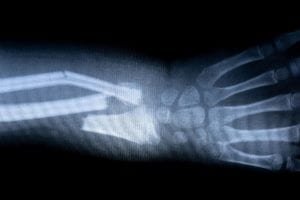

3. Hand and Wrist Fractures

Slip or trip and fall accidents are the most common cause of broken wrists and hand fractures. A fractured hand or wrist presents an increased risk of nerve damage, disability, and arthritis.

Your doctor will usually diagnose a fracture with some x-rays and a physical examination.

The doctor will move the broken bones into correct alignment manually before immobilizing the bones with a splint or cast. Complicated fractures may need surgical repair, with pins or rods in place to hold the bones together.

Diagnostic test results are critical. Preferably, you will want test results and exam records from as close to the time of the injury as possible. An x-ray taken during an emergency room visit immediately after an accident gives an insurance adjuster or jury a clear picture of how you felt immediately after you were injured.